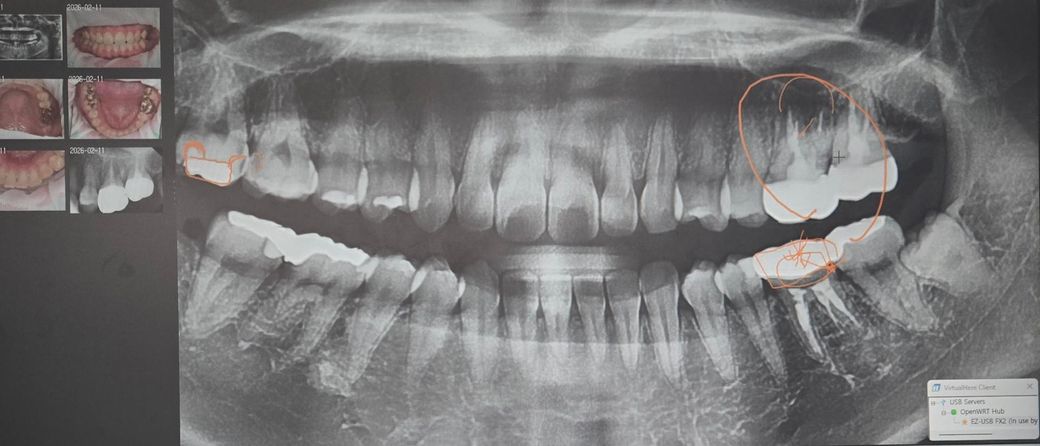

해당사진은 마지막에 갔던 치과에서 진단받은내용입니다

왼쪽부터 인접면(재신경치료) , 오른쪽상하단 발치및 임플란트 고려해볼필요있다고 하셨습니다;

충치3곳이 맞나요? 오른쪽 상단 말고는 통증도 없었습니다....

엑스레이상 표시된 부위는 충치로 의심되는 상황은 맞습니다 왼쪽은 신경치료가 되어있으니 추가로 충치가 생겨도 통증은 없을 수도 있고요

일단은 오른쪽부터 차근차근 치료받아보세요 어차피 양쪽 다 한번에는 힘들어서 못합니다

왼쪽도 염증으로 잇몸뼈가 녹고 있는 양상이나 아주 급격하게 악화되고 그러진 않을것 같네요